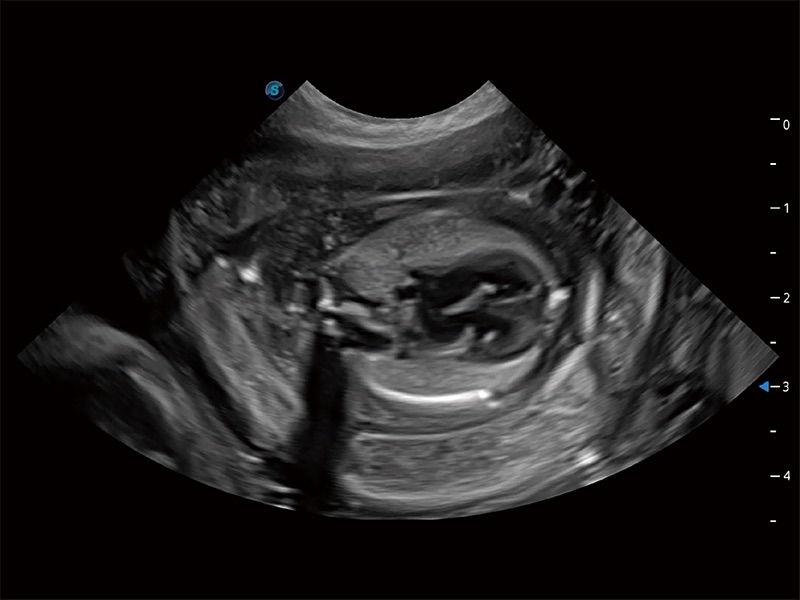

动物是人类最亲密的朋友和最值得信赖的伙伴。百老汇电子游戏官网也一直致力于探索动物专用的超声影像解决方案。全新推出的ProPet系列,是百老汇电子游戏官网在动物超声影像智能化、专业化、精准化的一次跨越式革新。动物不能用言语来表述自己的不适,通过超声影像,ProPet系列搭建了动物医生与不同物种沟通的“桥梁”,为动物医生注入了“治愈之力”。 ProPet 80 是百老汇电子游戏官网匠心打造的一款高端动物专用彩超,采用性能卓越的全新硬件架构,极大提升超声系统的运行效率和数据处理能力,帮助动物医生从容应对日益增多的挑战性病例和日益多样化的临床需求。

高性能和先进的临床应用工具可以为动物医生提供临床信心。ProPet 80 搭载了先进的腹部和浅表应用工具,帮助医生在日常临床实践中发挥前所未有的作用。

ProPet 80 全新的动物超声智能软件和丰富的探头群,为动物医生提供了高清晰度和精细分辨率的图像,无论在宠物、马科、畜牧还是实验室动物等应用中都可以轻松应对,为您的日常工作带来满意的体验。